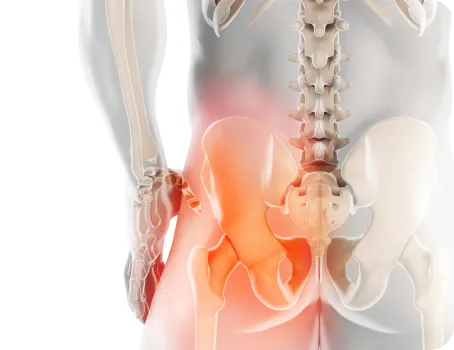

골반

허리는 골반위에 수직으로 서 있는 구조물이기 때문에 골반의 틀어짐은 필연적으로 허리를 틀어지게 만들어 허리에 많은 스트레스를 유발합니다. 만약 골반이 뒤로 기울어진 골반후방경사가 있다면 디스크탈출증을 더욱 악화시키며, 한쪽으로 회전되고 기울어진 골반은 체중이 집중되어 허리디스크와 협착증을 악화시키기 때문에 골반교정은 매우 중요합니다.